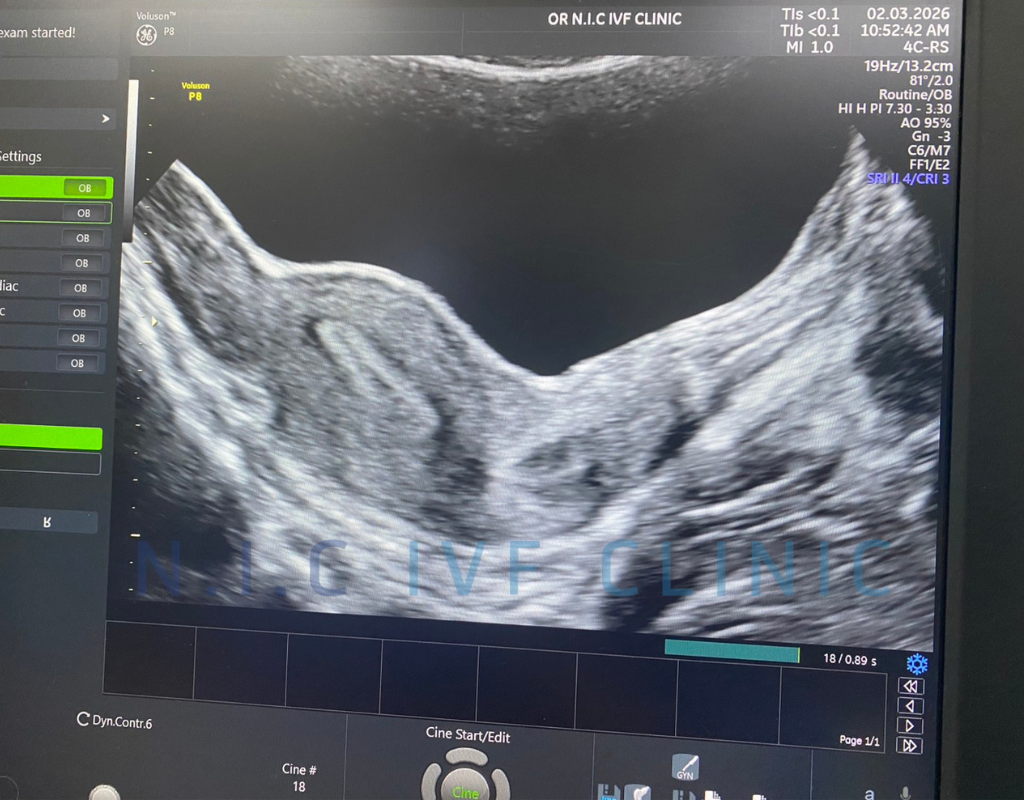

During embryo transfer, the physician uses abdominal ultrasound to guide the catheter carrying the embryo into the correct position within the uterine cavity.

When the bladder is moderately full, it helps create a clearer ultrasound image of the uterus. This allows the physician to see the uterine cavity more clearly and place the embryo in the most appropriate location with greater precision.